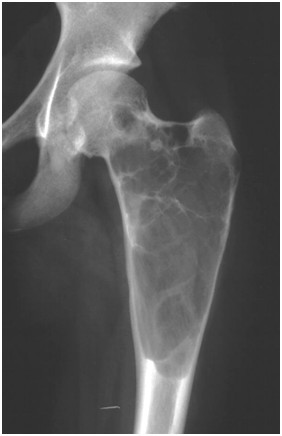

Przedstawiony poniżej radiogram 17-letniego chłopca wykazuje zmiany w odcinku bliższym kości udowej. Zmiana została wykryta przypadkowo, a chory do tej pory nie zgłaszał żadnych dolegliwości. Obraz radiologiczny sugeruje :

Pytanie 66